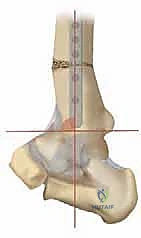

2. التصوير بالأشعة السينية بوضعية الوقوف (Weight-bearing X-rays)

هذا هو حجر الأساس في التشخيص. الأشعة العادية والمريض مستلقٍ لا تظهر الحجم الحقيقي للتشوه. يطلب الدكتور هطيف صوراً خاصة والمريض يحمل وزنه كاملاً على قدميه.

* المنظر الأمامي الخلفي (AP View): لتقييم المسافة المفصلية وتحديد زاوية سطح الساق (Tibial Anterior Surface Angle - TAS).

* منظر سالتزمان (Saltzman View): وهو منظر إشعاعي متخصص جداً لتقييم محاذاة الكعب الخلفي بالنسبة لمحور الساق، وهو أمر حاسم في التخطيط الجراحي.

التخطيط الجراحي: دقة المليمتر مع الدكتور محمد هطيف

النجاح في جراحة قطع العظم لا يحدث في غرفة العمليات، بل في مرحلة التخطيط التي تسبقها. يستخدم الدكتور هطيف برمجيات حاسوبية متقدمة لتحليل صور الأشعة وحساب زوايا التصحيح المطلوبة بدقة متناهية.